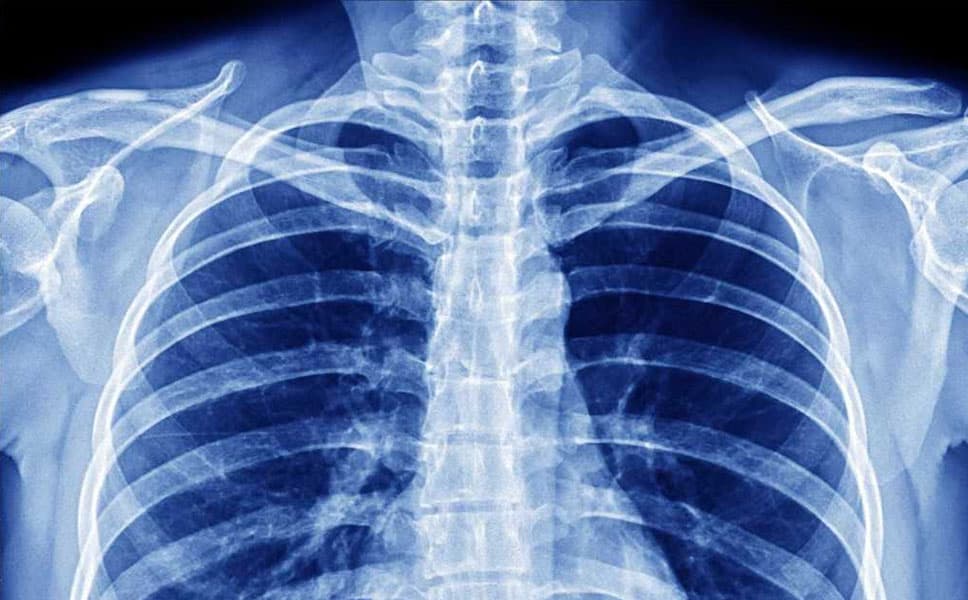

Una semplice radiografia del torace potrebbe svelare i segni della polmonite da Covid-19 nei pazienti asintomatici o con pochi sintomi: è quanto emerge dallo studio condotto nel focolaio di Codogno dall’Irccs Istituto Ortopedico Galeazzi di Milano in collaborazione con le Università degli Studi di Milano, Pavia e Palermo, il centro Medical Radiologico di Codogno e la Radiologia della Casa di Cura San Camillo di Cremona. I risultati sono pubblicati sulla rivista Radiology.

La ricerca si è focalizzata sull’analisi retrospettiva delle radiografie al torace eseguite post-quarantena su pazienti che non riferivano particolari malesseri oppure lamentavano solo sintomi piuttosto vaghi, come febbricola (sotto 37,5°C) e avvisaglie parainfluenzali. In una sola settimana è stato riscontrato come 100 radiografie al torace su 170 (circa il 60%) presentavano immagini riconducibili a una polmonite interstiziale bilaterale, quindi altamente sospette e riferibili alla polmonite correlata al Covid-19.